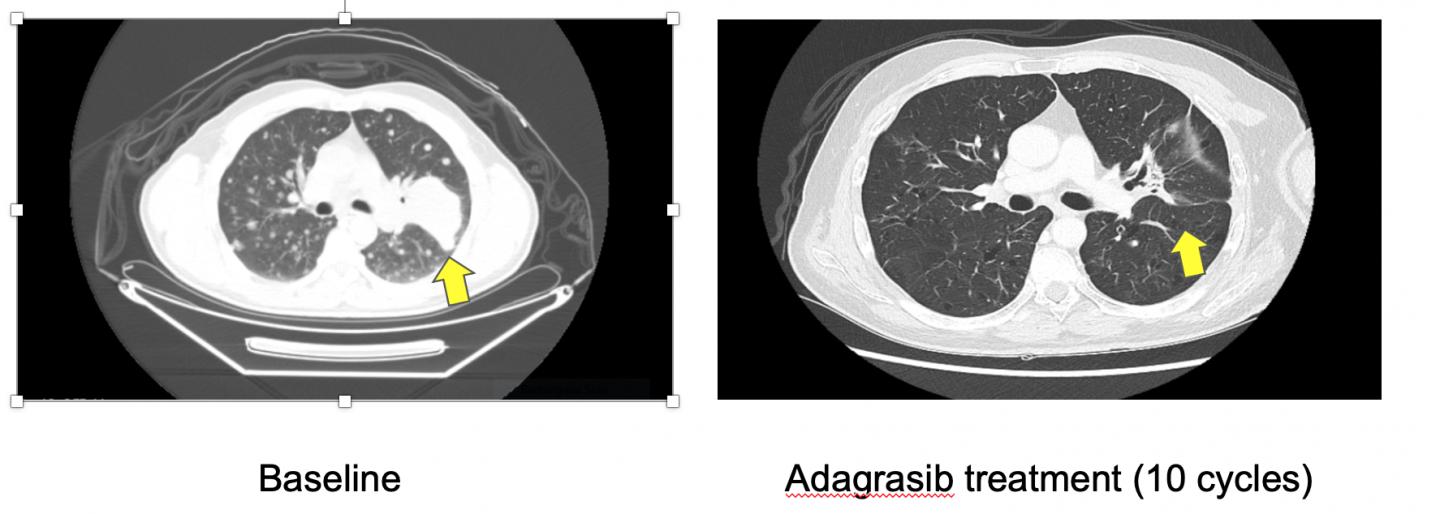

image: Patient CT scans before and after treatment with adagrasib. Yellow arrow marks location of main tumor.

Dr Pasi A. Jänne, Director of the Lowe Center for Thoracic Oncology, Dana Farber Cancer Institute, and Professor of Medicine at Harvard Medical School, Boston, USA, presented the results for 79 NSCLC patients up to 30 August 2020 to the Symposium. He said: "Among 51 patients for whom we had information on the clinical activity of adagrasib, 45% had an objective response, meaning that their tumours shrank by 30% or more and did not grow or spread to other parts of the body. This includes five patients who had an unconfirmed partial response by 30 August and who were subsequently confirmed as having a partial response in later scans. The disease control rate was 96%, meaning that 49 out of the 51 patients showed a partial or complete response or had stable disease."